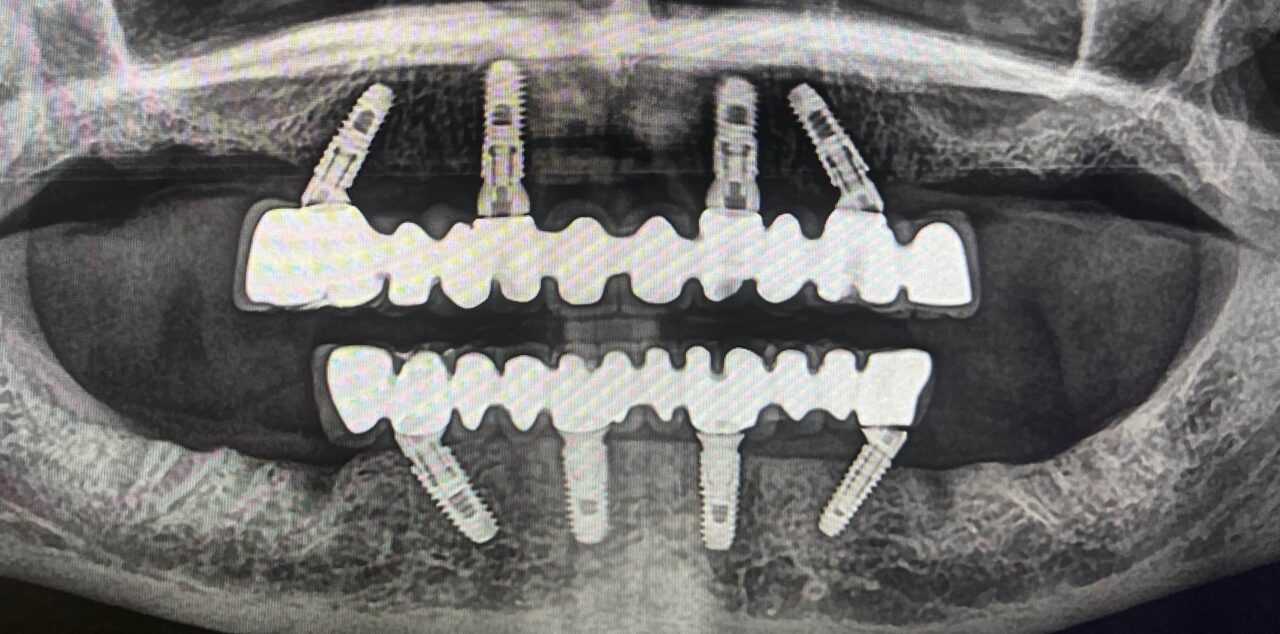

Fester Zahnersatz mit

All on 4

Die All-on-4-Methode ermöglicht eine feste Zahnprothese auf nur vier Implantaten – ideal bei Zahnverlust im gesamten Kiefer. Der Eingriff ist minimalinvasiv und bietet eine schnelle Wiederherstellung von Funktion und Ästhetik. Patienten profitieren von kürzeren Behandlungszeiten, hoher Stabilität und einem natürlichen Lächeln. Diese Lösung ist besonders geeignet für Menschen mit geringer Knochensubstanz.